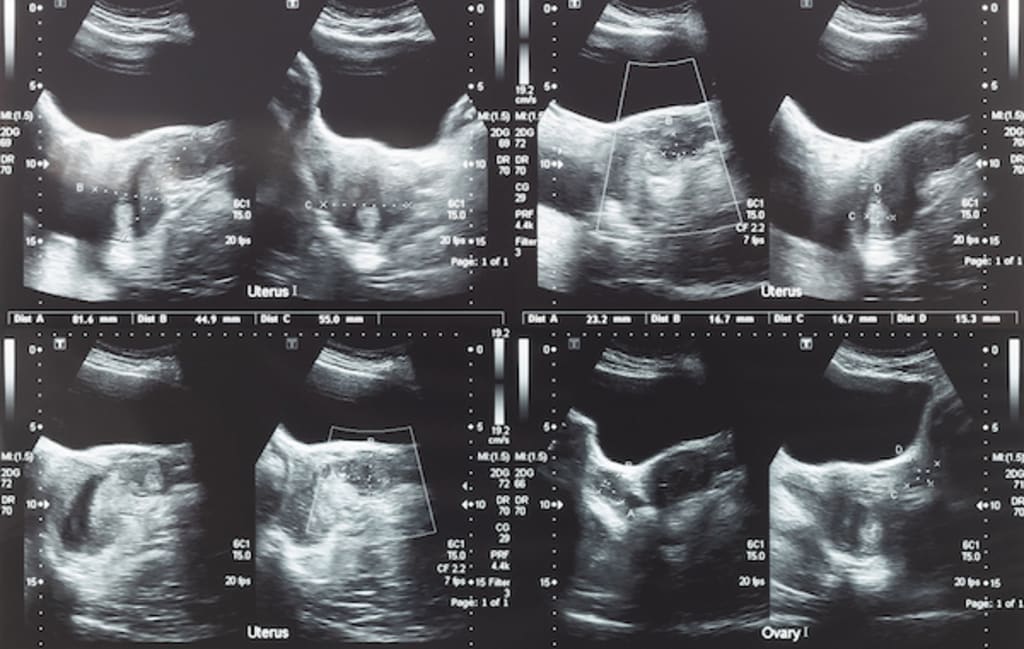

10 Main Treatments for Uterine Fibroids

Despite the fact that uterine fibroids are fairly common, dealing with them isn't always easy. The decision to treat these benign muscle tissue growths is based on a number of criteria, including when and how to try eliminating or shrinking them, as well as whether they even need to be treated in the first place.